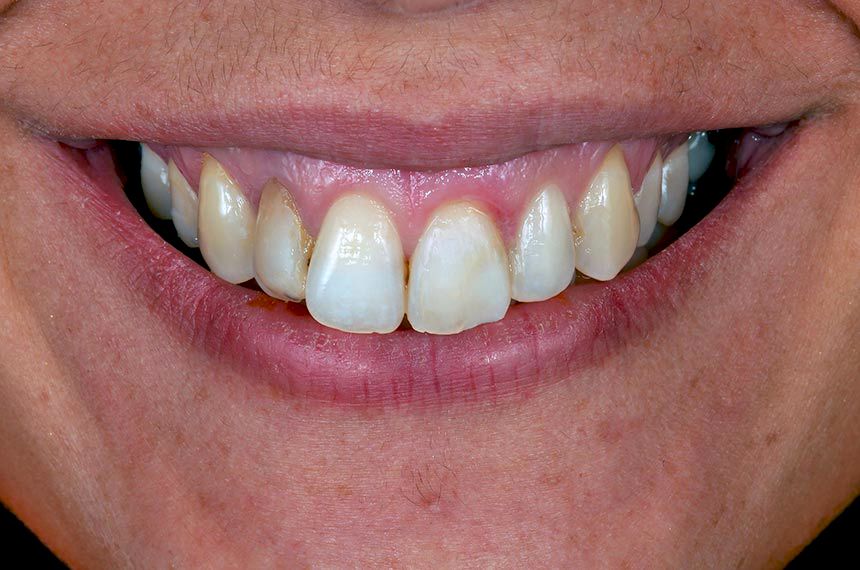

Labial view of the provisional restoration 3 months after the implant surgery (Fig. 14). Note the preservation of the tissue architecture. The provisional restoration was retrieved (Figs. 15, 16). An implant impression was made using a custom impression coping to transfer a record of the healed anatomic tissue to the laboratory (Fig. 17). A definitive customized hybrid abutment on Straumann® Variobase® crown with specific gingival emergence profiles and anatomical shape established by the provisional restoration was fabricated (Figs. 18, 19). The finished abutment was torqued to 35 Ncm, and a provisional PMMA CADCAM restoration was cemented (Figs. 20-22). Three months later a definitive impression was recorded using the lithium disilicate CADCAM core of the definitive restoration as a snap-on abutment coping (Fig. 23). The abutment was never removed during the prosthetic procedures. The definitive restoration was cemented using a resin cement (Figs. 24, 25). The gingival complex surrounding the implant has remained stable. The peri-implant soft tissue was healthy, with no signs of inflammation (Figs. 26-30). The final periapical radiograph revealed no peri-implant bone loss radiographically (Fig. 30).